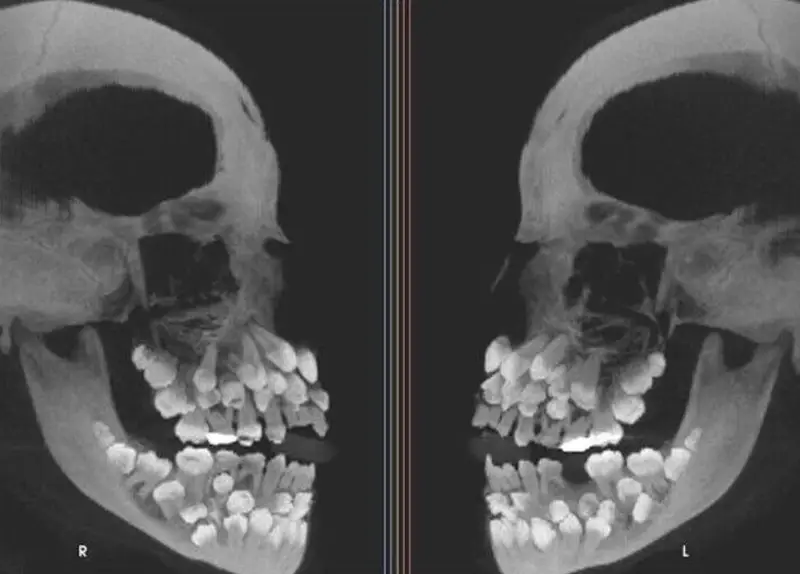

#7 Má tri rady zubov